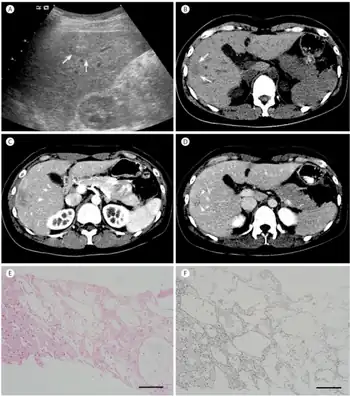

| The CT scan of a patient with peliosis hepatis (left): The follow-up CT (right) after 7 years shows full remission. | |

Peliosis hepatis is an uncommon vascular condition characterised by multiple, randomly distributed, blood-filled cavities throughout the liver. The size of the cavities usually ranges between a few millimetres and 3 cm in diameter.[1] In the past, it was a mere histological curiosity occasionally found at autopsies, but has been increasingly recognised with wide-ranging conditions from AIDS to the use of anabolic steroids. It also occasionally affects spleen, lymph nodes, lungs, kidneys, adrenal glands, bone marrow, and other parts of gastrointestinal tract.[2]

Two morphologic patterns of hepatic peliosis were described by Yanoff and Rawson.[13] In the phlebectatic type, the blood-filled spaces are lined with endothelium and are associated with aneurysmal dilatation of the central vein; in the parenchymal type, the spaces have no endothelial lining and they usually are associated with haemorrhagic parenchymal necrosis. Some consider both patterns to be one process, initiated by focal necrosis of liver parenchyma, observed in parenchymal type, progressing into formation of fibrous wall and endothelial lining around haemorrhage of phlebectatic type. Fibrosis, cirrhosis, regenerative nodules, and tumours may also be seen.

Diagnosis

The condition is typically asymptomatic and is discovered following evaluation of abnormal liver function test. However, when severe, it can manifest as jaundice, hepatomegaly, liver failure, and haemoperitoneum.